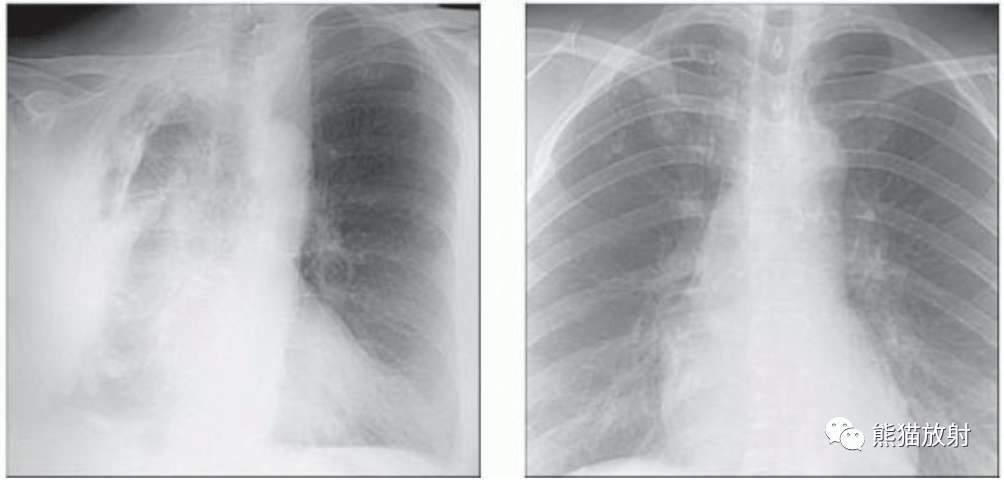

肺炎的肺部x光片图片

肺炎的肺部x光片图片,